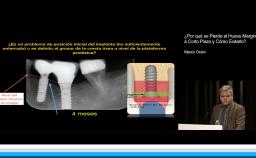

La patología periodontal es un hallazgo muy común en nuestras consultas. Además constituye uno de los factores de riesgo más importantes en el tratamiento implantológico por motivos tan diferentes como son los estéticos, quirúrgicos, biológicos, biomecánicos y hasta filosóficos si tenemos en cuenta el dilema que a veces se nos plantea en la clínica sobre extraer o no extraer y cuándo hacerlo.

En esta conferencia, el Dr. Rodrigo presta especial atención a todos los aspectos de riesgo englobados en el manejo del paciente periodontal en tratamiento con implantes, efectuando una exhaustiva revisión de la evidencia existente y con abundante iconografía. Se revisan factores de riesgo tales como el biológico, incluyendo tanto la genética como la microbiología pasando por el diseño personalizado de la prótesis, el riesgo estético y las limitaciones de nuestro tratamiento respecto a las expectativas de los pacientes y finalmente el riesgo quirúrgico o como simplificar nuestros procedimientos en estos pacientes de alto riesgo, mediante el empleo de implantes cortos, estrechos, angulados e inmediatos.